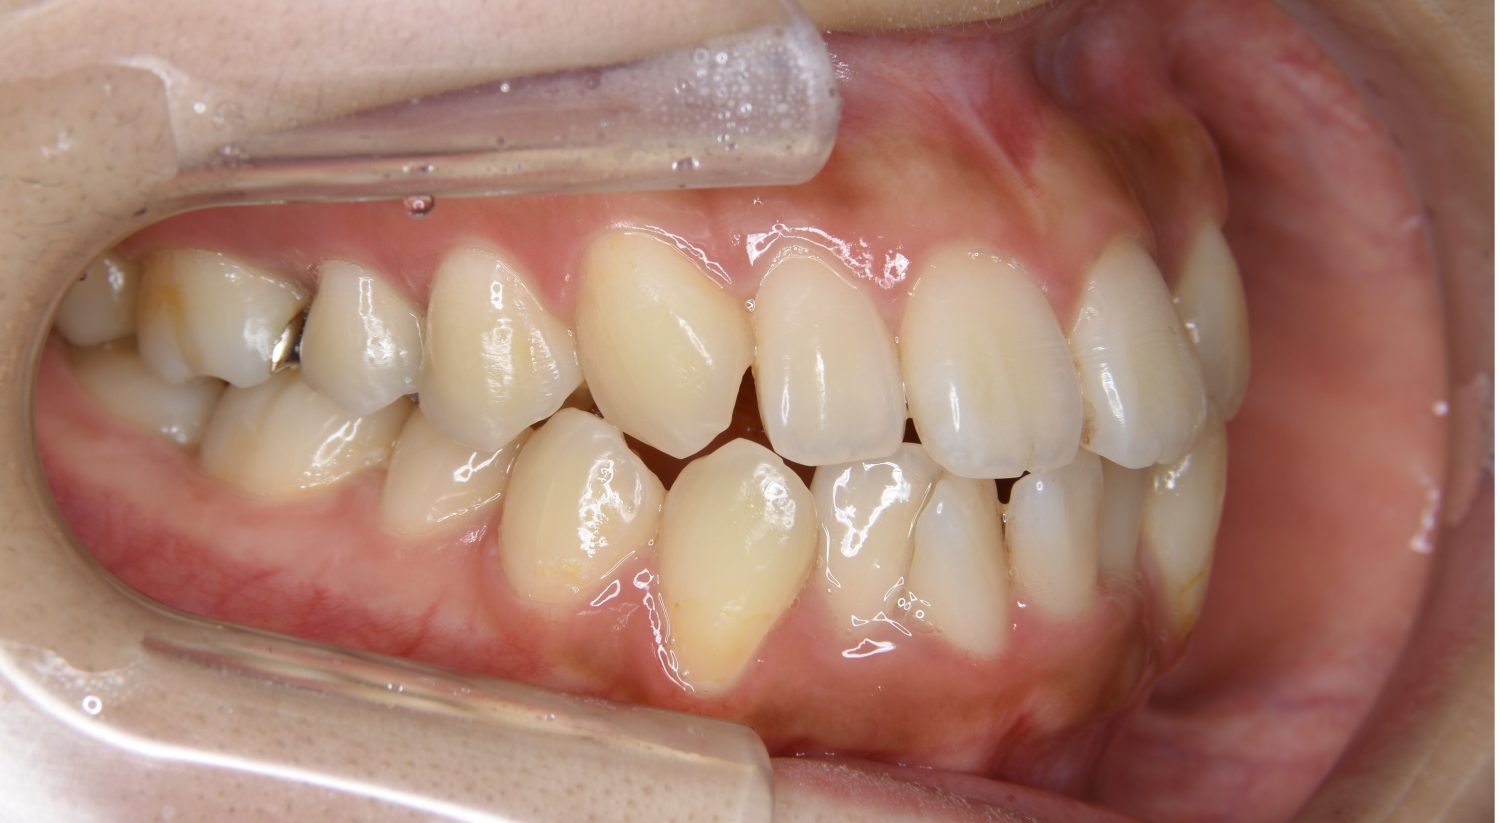

叢生の症例紹介①

Before

主訴

前歯のガタガタが気になる。

治療内容

上顎左側第一小臼歯を抜歯し、アライナー(インビザライン)にて治療を行いました。

左上の側切歯が完全に内側に入り込んでいる状態でした。左上の第一小臼歯のみ抜歯を行い治療を行うことで機能面および審美面を改善しました。